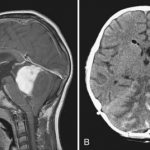

Пациентам назначают МРТ головного мозга. Это обследование помогает выявить этиологию эпилептиформного синдрома. Очаги глиоза на снимке указывают на повреждение нейронов вследствие травмы или инсульта. Глиозными изменениями врачи называют разрастание вспомогательных клеток головного мозга. Обычно это отмечается после гибели нейронов.

Важным методом дифференциальной диагностики является электроэнцефалограмма. При эписиндроме ЭЭГ может не показывать патологических изменений. Ведь очаги возбуждения в головном мозге появляются только перед приступом. При эпилепсии электрическая активность коры мозга повышена постоянно.

С целью исключения органического поражения ЦНС назначают стандартные инструментальные исследования (ЭЭГ, КТ, МРТ и т.п.). Важным и информативным методом уточняющей диагностики выступает экспериментально-психологическое обследование, которое в ряде случаев выявляет определенную личностную деформацию и/или сверхценные для данного больного стимулы, темы, ситуации и другие факторы, связанные с психологической первопричиной и могущие служить триггером для «запуска» диссоциативных конвульсий.